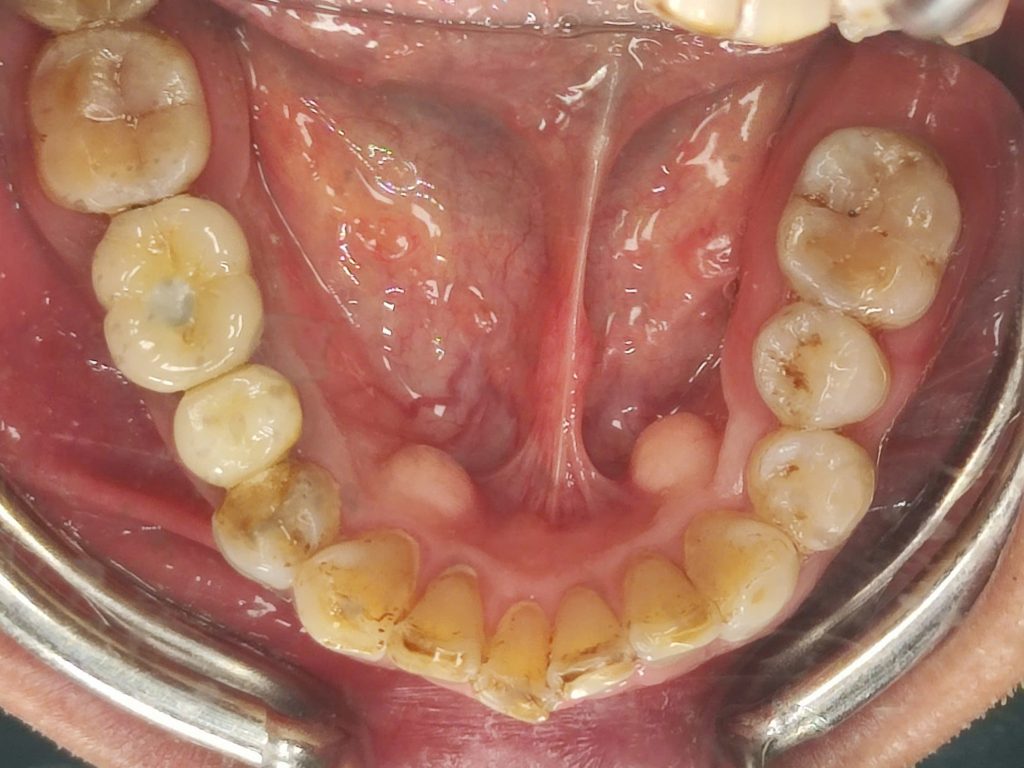

Cùng tìm hiểu quy trình cấy ghép Implant an toàn tại Nha Khoa Ace Smile qua trải nghiệm thực tế của anh Cường.

Bước 1 – Thăm Khám & Chụp XQ 3D

Bước 2 – Lên kế hoạch điều trị cá nhân hoá